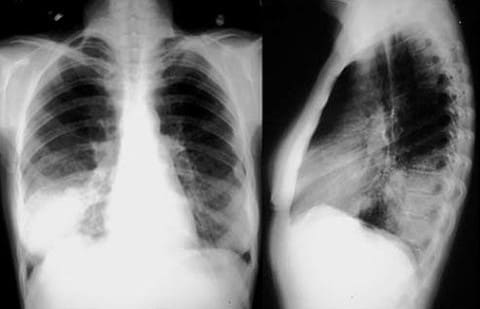

Пневмония – воспаление легочной ткани, основная масса которой вызывается бактериями, в частности пневмококком, однако встречаются и пневмонии другой этиологии. Основными жалобами являются повышение температуры тела от субфебрильной до фебрильной, нарастающая слабость, снижение аппетита, озноб и повышенная потливость, общее недомогание, усиливающийся кашель продуктивного характера (с мокротой). Характер мокроты будет полностью зависеть от причины, вызвавшей заболевание (более подробно в статье: пневмония).

Пневмония

слизистой гортани, трахеи), бронхоскопия, рентгенологическое исследование легких (выявление характера процесса при бронхите, пневмонии, степени распространения воспаления, динамики лечения).